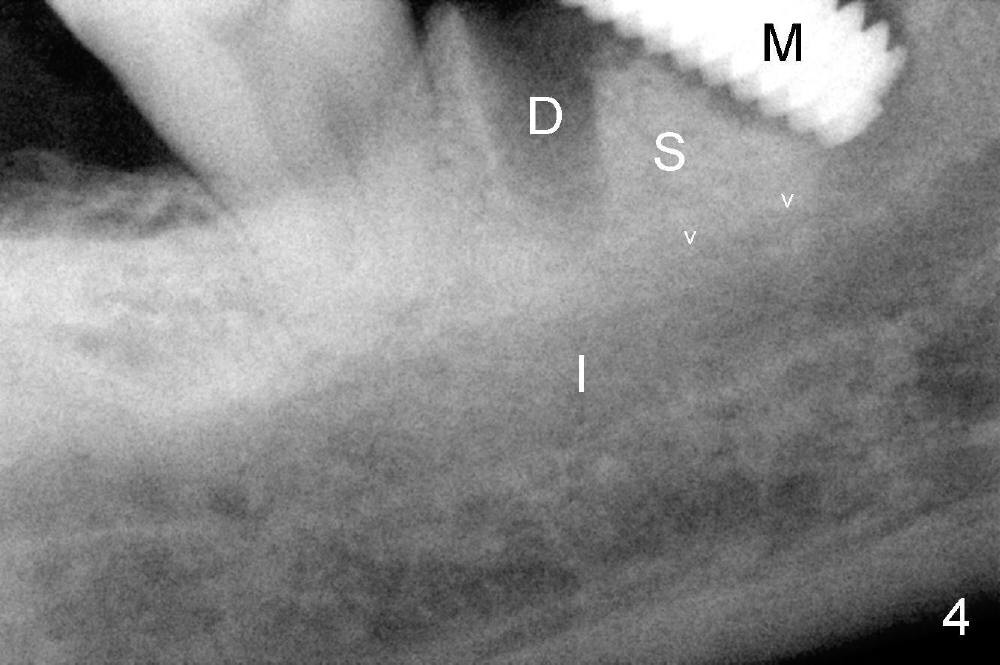

There are three potential spaces for the immediate implant: the mesial and distal sockets and the septum. First at all, the tooth should be extracted with curettage of granulation tissue from the mesial apical lesion. The latter turns out to be difficult, since the bottom of the mesial socket has abrupt transition into a narrow neck, which look and feels like the IAN. To determine the depth of the lesion relative to the IAN, PA is taken (Fig.3) without too much information. When a radiopaque material in placed in the mesial socket (Fig.4 M), the lesion has apparently not extended to the IAN. Curettage of the remaining granulation tissue is now an easy task. Finally bleeding comes from a small hole, as indicated by arrowhead. Therefore the special structure is a branch of the inferior alveolar vessels.

As to where to place an implant, we try to engage the largest tap (8 mm in diameter) into the mesial socket without binding. The buccal plate of the mesial socket is missing. It is risky to extend osteotomy in the mesial socket. Besides, the septum (Fig. 4 S) is not as tall as the distal socket (D). It appears that the distal socket is the safest place to place an implant. Furthermore, no drill is used for distal osteotomy. Instead two osteotomes (3.5x15 and 4x15 mm tapered osteotomes) are used to expand the distal socket with intention to push the septum mesially. Since the bone density is high, the osteotomes seem not to work as effectively as expected. Then a 4.5x17 mm tap is placed at the depth ~ 14 mm with stability (Fig.5). Finally a 5x14 mm tissue-level implant is placed with insertion torque >60 Ncm (Fig.6). Allograft is placed in the mesial socket and buccal aspect of the distal socket, followed by insertion of collagen plug and membrane (Fig.7). After insertion of an abutment (Fig.8 (taken 6 days postop) *), perio dressing (P) is applied to cover the wound. There is no postop paresthesia.